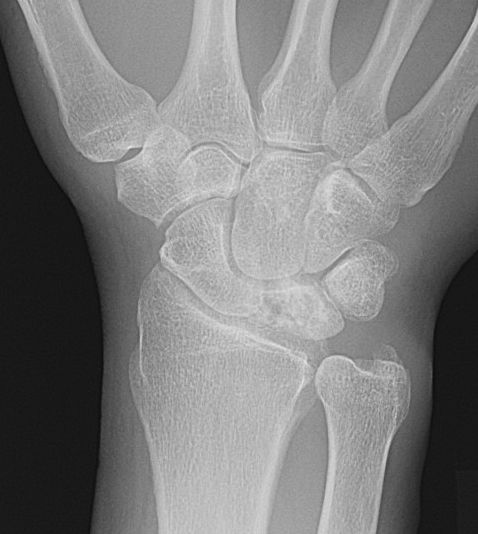

Stadium 3A: Kollapsad lunatum, kapitatum förflyttad proximalt [2]

Slätröntgen och T1-viktad MR-bild av lunatummalaci stadium 3A